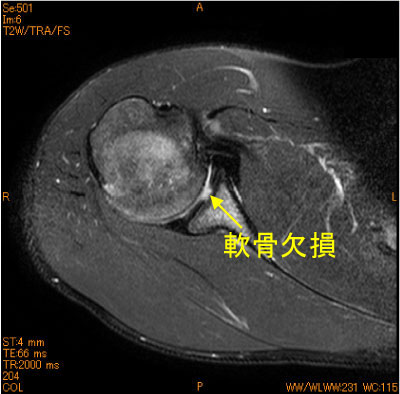

関節窩中央の軟骨欠損-肩関節MRI-

10代男性、投球時の痛み。

投球障害では、後上方関節唇損傷、棘下筋腱関節側部分断裂、Bennett lesionが知られているが、何があるか判らないの肩関節の障害である。

脂肪抑制T2 WIは不可欠のシークエンスである。

![]() Axial T2WI 脂肪抑制 |